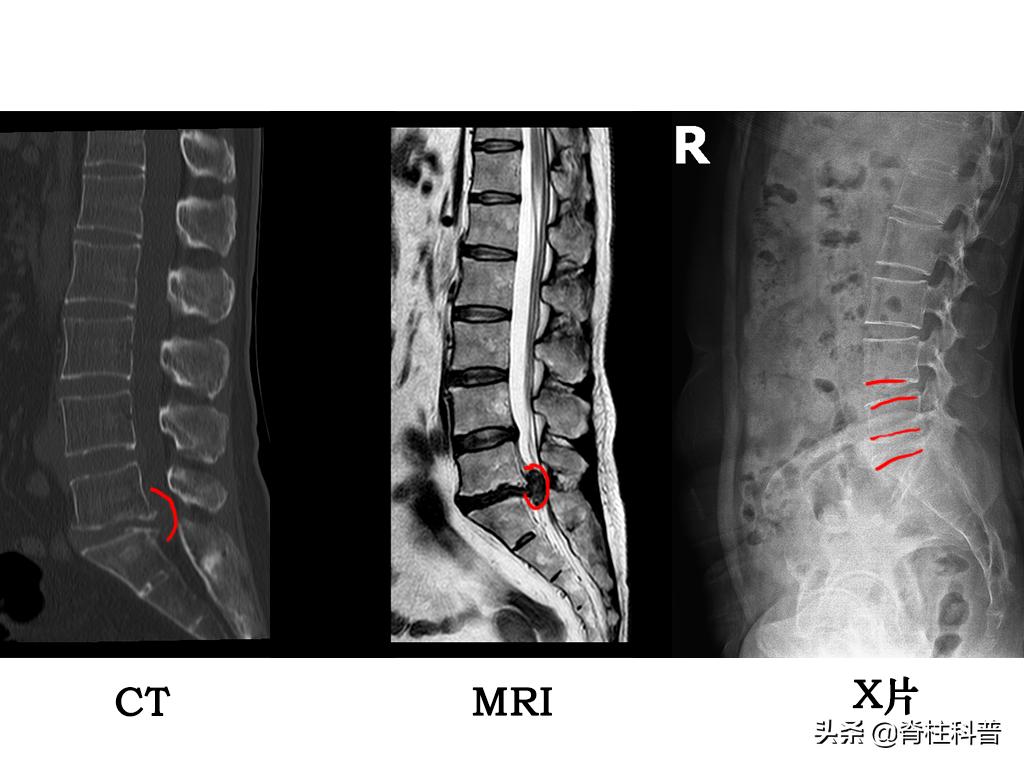

在解释上述问题的之前,我们先来直观的看一下MRI、CT、X线的图片。我找了一位发病经过最常见、求诊片子最凸显的病人做案例。来我科做手术的腰椎间盘突出症的患者多数为40-60岁年龄段(符合该病的发病年龄段)。

45岁女性患者,因“反复腰痛并左下肢疼痛3年余,再发并加重10余天”前来就诊的。

图片源自:南方医科大学第三附属医院脊柱外科

椎间盘突出的程度不同,脊髓、神经受压的情况不同,患者表现出来的症状不同,在临床治疗上会根据病情采用不同的方法,所以需要经过影像学进行鉴别诊断,以便更有效的实施治疗。